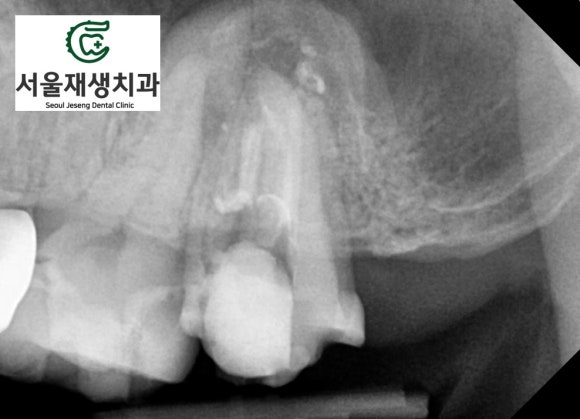

신경치료가 아주 잘된 것 같은데요...

그런데 왜 뿌리 끝 주위의

뼈가 녹아있는 걸까요?

CT를 촬영해보았습니다.

아뿔싸,

이전에 치료해주신 선생님이

신경관 하나를 놓치신 것 같습니다.

미처 청소되지 않은 신경관에서

지속적으로 오염물질이 흘러나와

뿌리 끝까지 내려간 것 같네요.

어금니의 경우

신경이 여러개이기 때문에,

조금만 방심해도 놓치는 신경이 발생할 수 있습니다.